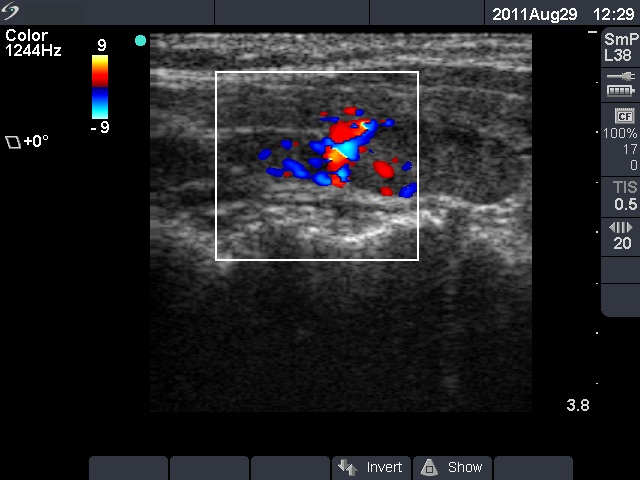

Follow-up examination 3 years later (second row of images):

Clinical presentation: the patient had no complaints.

Palpation: Both lobes were firm.

Laboratory tests: TSH 2.61 mIU/L on daily 125 microgram levothyroxine.

Ultrasonography: The thyroid was unchanged. The lesions in the dorsal part of the right lobe increased in size and a small hypoechogenic area appeared in the ventral part of the left lobe.

Aspiration cytology was performed from the lesion in the dorsal part of the thyroid. We gained only scattered number of epithelial cells without any atypia.

Wash-out thyroglobulin and parathormone levels were determined, the former was 74.4 ng/mL while the latter was above 474 pg/mL.

A repeat blood test was performed. Serum thyroglobulin resulted in 11.9 ng/mL while serum parathormone level did in 180.7 pg/mL. Serum calcium was 2.94 mM/L, serum phosphorus 0.69 mM/L.

Scintigraphy disclosed parathyroid enlargement not only in the right but even in the left side.

Surgery was performed. Histopathology disclosed hyperplasia of all four parathyroids.